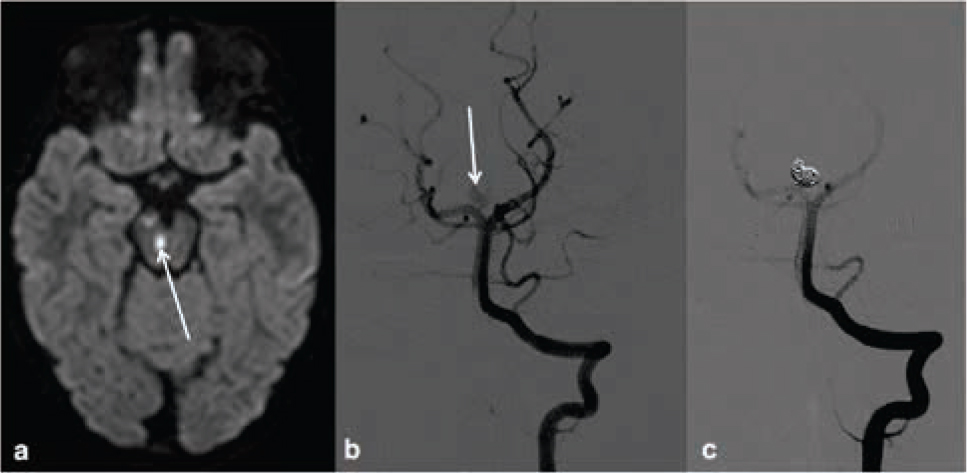

Vascular occlusive interventions provide minimally invasive treatment alternatives to conventional neurosurgical operations and are the only choice in cases that are surgically inaccessible. Cerebral aneurysm can be treated as scheduled intervention or, in case of emergency, by endovascular coiling with or without stents in order to induce thrombotic occlusion of the aneurysm. Outcome of patients treated with coiling is better than after surgical clipping (Figure 1), but early re-perfusion occurs more fre-quently [4]. Intravascular administration of glue (n-butyl cyanoacrylate), dehydrated alcohol or liquid embolics (Onyx®) into the arterial feeder vessels of arteriovenous malformations or fistulas causes vascular obliteration [5]. Combination with radiation and/or surgery is necessary in some cases. In the case of neoplasms, embolization of supply vessels with particles or coils prior to surgical removal or palliative treatment reduces bleeding complication.

Unusual case of a three year old girl with an incidentally found partially thrombosed intracranial aneurysm. The girl presented with oculomotoric palsies due to small brain stem and mesencephalic (arrow) infarctions found in diffusion weighted MRI (a). Digital subtraction angiography with injection of the left vertebral artery shows the aneurysm of the right proximal posterior cerebral artery (arrow) prior (b) and after (c) endovascular occlusion with platinum coils.